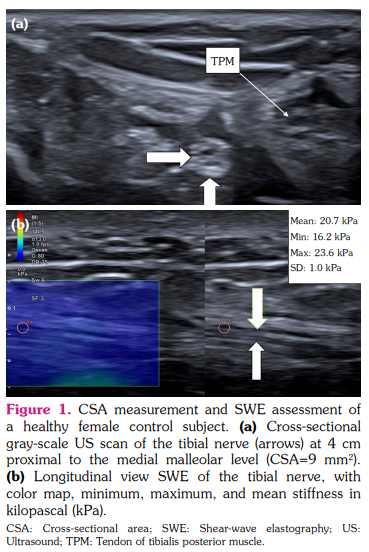

Tibial nerve was examined in the transverse and longitudinal planes at a distance of 4 cm proximal to the tip of the medial malleolus. The correct imaging plane was confirmed by tendinous landmarks, such as the flexor digitorum longus and flexor hallucis longus tendons, and the posterior tibial vessels.[16] CSA was measured by the use of a continuous boundary trace of the nerve directly over the epineurium on transverse images (Figures 1, 2).

Shear-wave elastography was performed by careful handling of the transducer during transport and mounting to avoid compression force. The skin surface was coated with ample coupling gel before placing the transducer, which was used with light force and kept stable during image acquisition. TN was first identified transversely, and then the transducer was rotated 90° to acquire a longitudinal image of the nerve in the parallel direction to the fiber orientation.[16]

The mean CSA value was 22±5.7 mm2 in patients with SSc and 12.65±3.4 mm2 in healthy controls. The mean stiffness value was 23.12±14.5 kilopascal (kPa) in patients with SSc and 15.5±3.27 kPa in healthy controls. The CSA and stiffness values of the right TN were significantly higher in SSc patients than in healthy control subjects (p<0.001 and p=0.015, respectively; Table 2).